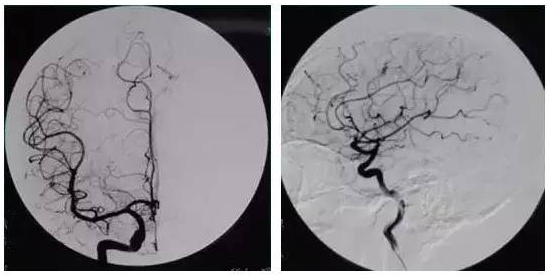

五分钟看懂全脑血管造影

图片尺寸550x275